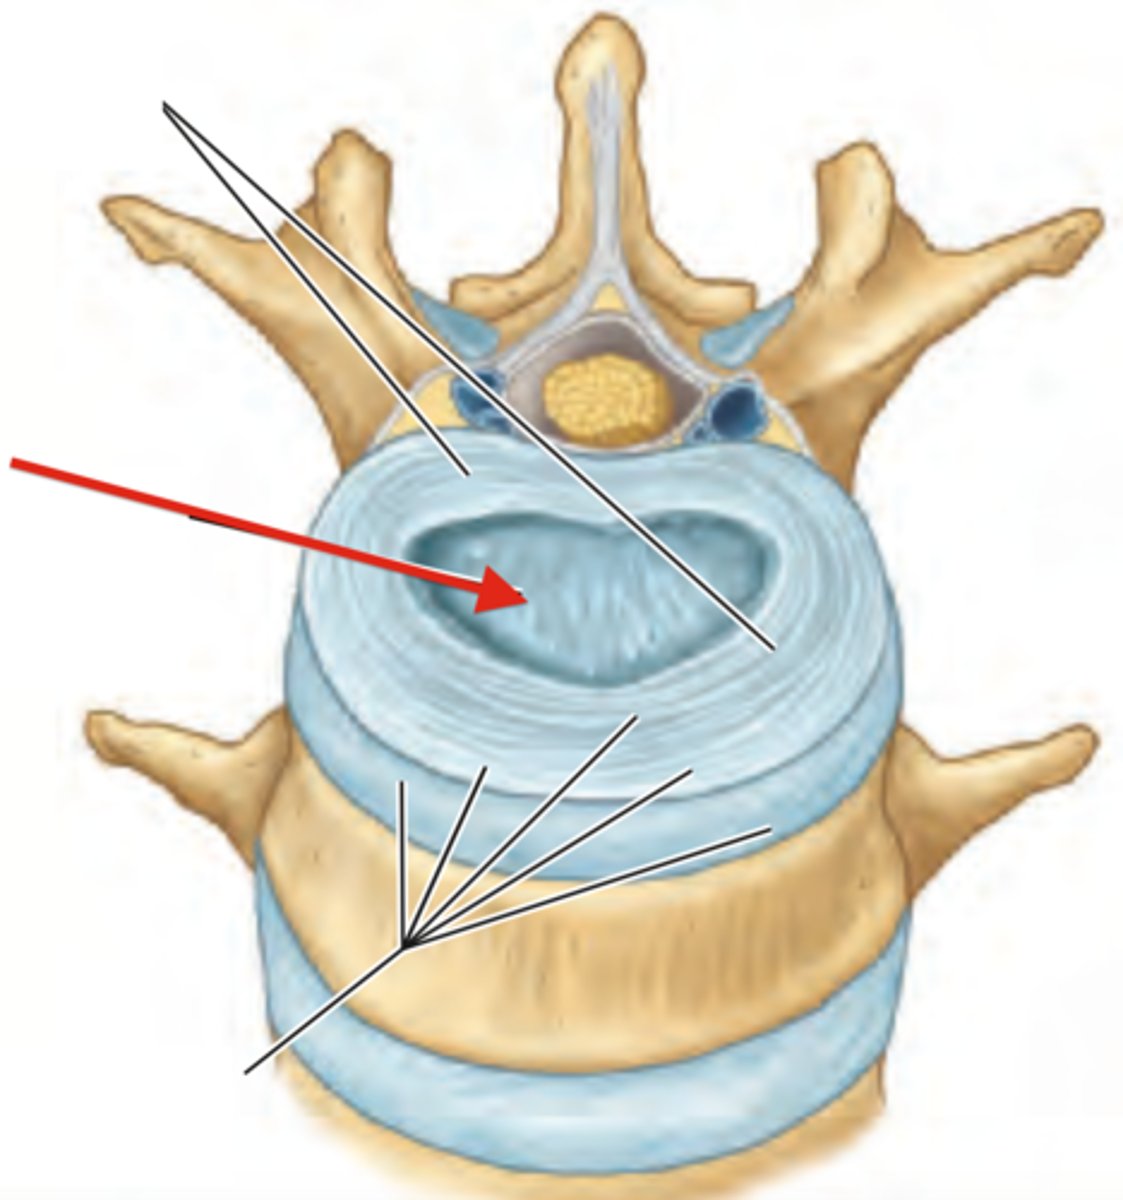

anulus fibrosus

nucleus pulposus

Shock absorbtion

what is the purpose of the intervertrebral disks

intervertebral foramen

passage for spinal nerves

what is the purpose of the intervertebral foreman